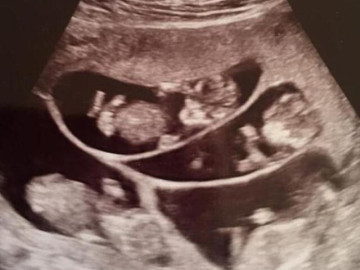

Đi tiêm kích trứng, người phụ nữ bất ngờ biết mình đang mang thai 9 con

Một người phụ nữ ở Trung Quốc đã rơi vào trạng thái vô cùng hoảng hốt khi biết rằng mình không chỉ thụ thai thành công sau khi tiêm thuốc kích trứng,...

Sinh đôi và đa thai